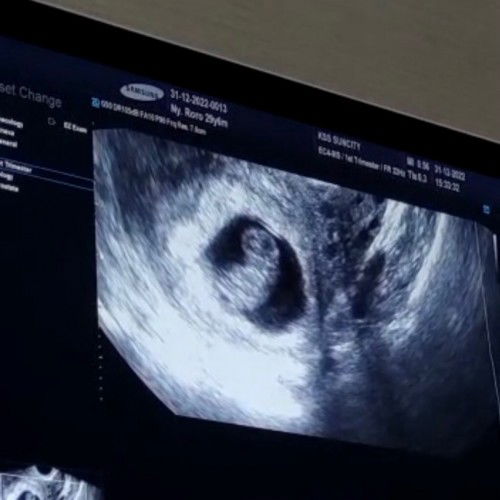

Assalamualaikum bun, Semalam saya kontrol ke obgyn, saya sampaikan keluhan saya 4hari lalu jika saya merasa nyeri dibawah perut selama 2 hari. Ternyata saat usg kedua ini, terdeteksi ada nya miom 5,2cm di depan, usia kehamilan 13w. Tapi posisi miom tersebut akan dipastikan lagi selama bertambahnya usia kehamilan. Sedih bun, jadi kepikiran. Dr bilang itu jinak, tapi posisi keberadaannya bisa menghalangi jalan lahir☹️ Bunda2 ada yg pengalaman riwayat kehamilan ada miom? mayoritas bisa normal atau harus sc ya bun? Saya juga lupa nanya ke dokter supaya uk miom tidak semakin membesar, pantangannya apa saja ya untuk makanan? Alhamdulillah kondisi janin sehat. #ingintahu #firstmom #miom